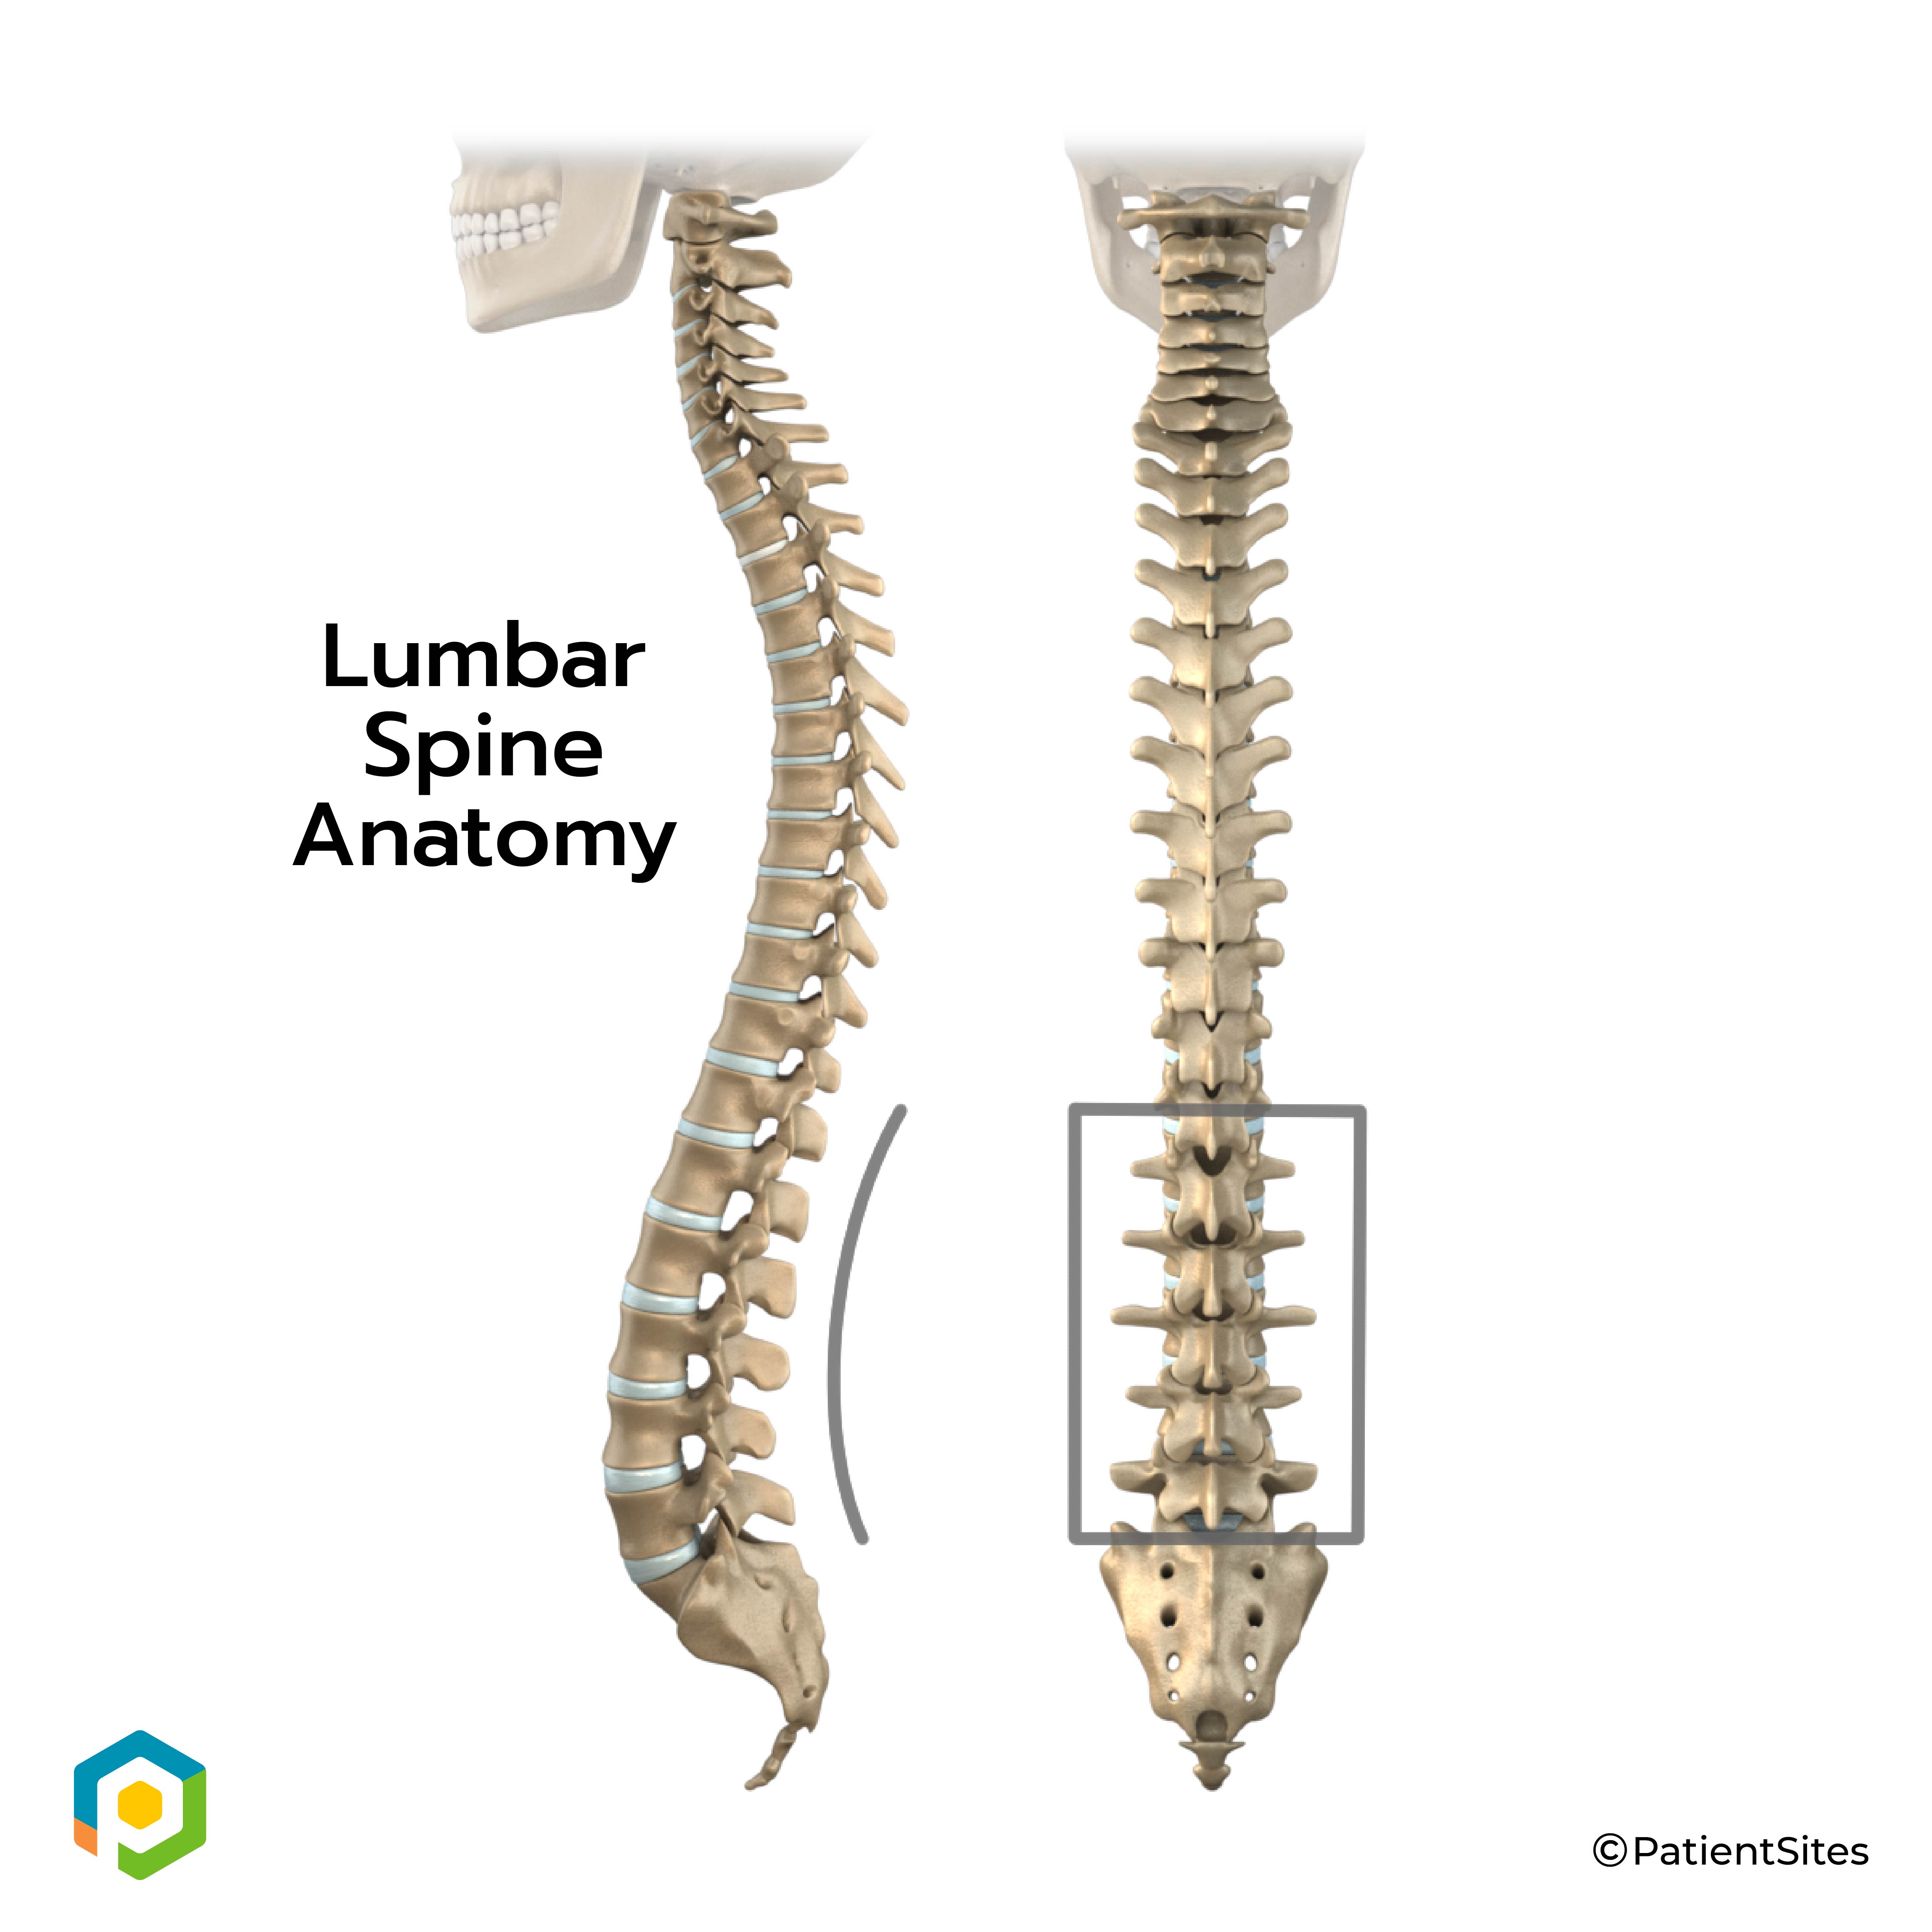

The human spine is made up of 24 spinal bones, called vertebrae. Vertebrae are stacked on top of one another to form the spinal column. The spinal column gives the body its form. It is the body's main upright support. The section of the spine in the lower back is known as the lumbar spine.

Lumbar Spine